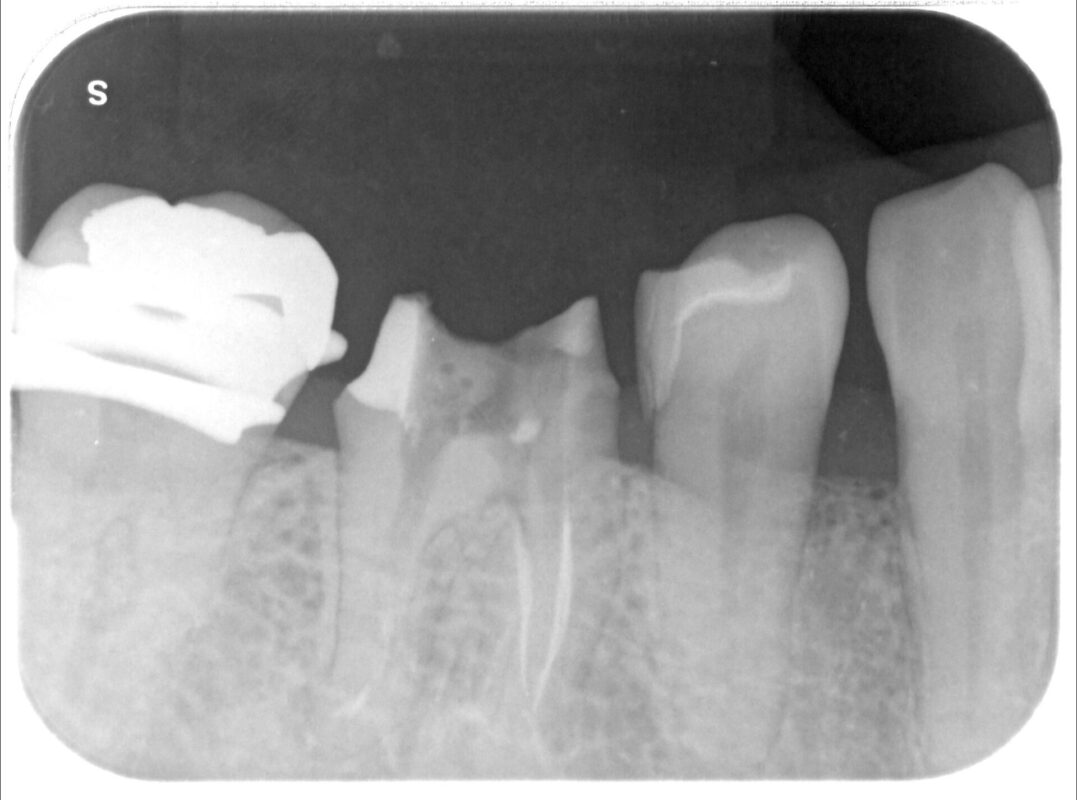

大まかにガッタパーチャを除去した状態です。

2時間以上かかって3本とも除去できました。

遠心根は先に根管充填終わっています。